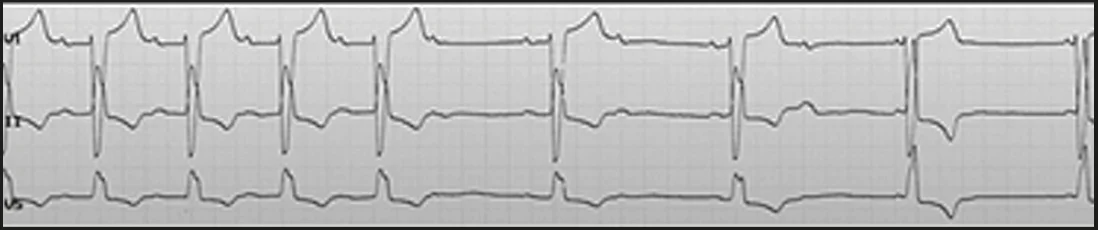

Пацієнт віком 80 років, має ТП 4:1, в анамнезі – неодноразові електричні кардіоверсії. Після чергової кардіоверсії у чоловіка на наступний день обірвався ритм, і було прийняте рішення її більше не проводити. Натомість пацієнтові призначили невелику дозу серцевих глікозидів та β-блокатор короткої дії. Через два місяці терапії (без ААП) ритм нормалізувався, який тримається вже понад рік (рис. 11).

Рис. 11. ЕКГ на тлі приймання β-блокатора і серцевого глікозиду

Однак у пацієнта було ТП 4:1, що означає, що в нього є схильність до порушення АВ-провідності. З часом його почали турбувати епізоди слабкості, й навіть мав місце синкопальний стан, що свідчило про прогресування порушень АВ-проведення, але при цьому зберігався синусовий ритм. Хворому було імплантовано кардіостимулятор.